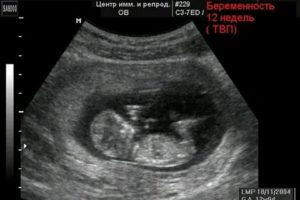

- УЗИ;